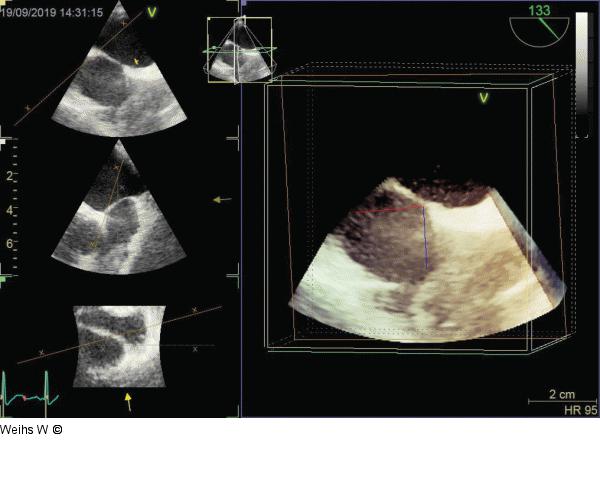

Abbildung 5: Raumforderung Transthorakale Echokardiographie mit dreidimensionaler Rekonstruktion der Raumforderung an der Spitze des Port- A-Cath. |

Transthorakale Echokardiographie mit dreidimensionaler Rekonstruktion der Raumforderung an der Spitze des Port- A-Cath. |